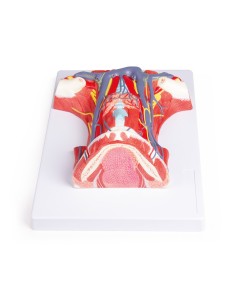

3B Scientific, modello anatomico funzionale di laringe: W42503

Dal cranio in 22 parti con incastri magnetici ai modelli di colonna vertebrale, da quelli di articolazioni a quelli di cuore, ogni pezzo della nostra collezione è progettato per un’immersione totale nello studio dell’anatomia umana. I nostri modelli, realizzati tramite scansioni di ossa vere, garantiscono un’esperienza tattile autentica e una fedeltà di peso quasi identica agli originali.

Essenziali per studenti e professionisti, i nostri modelli anatomici sono strumenti didattici che permettono di osservare le strutture anatomiche con precisione, eliminando la necessità di dissezioni o studi invasivi. Sono inoltre utili per spiegare ai pazienti le patologie, rendendo la comunicazione più efficace e risparmiando tempo prezioso.